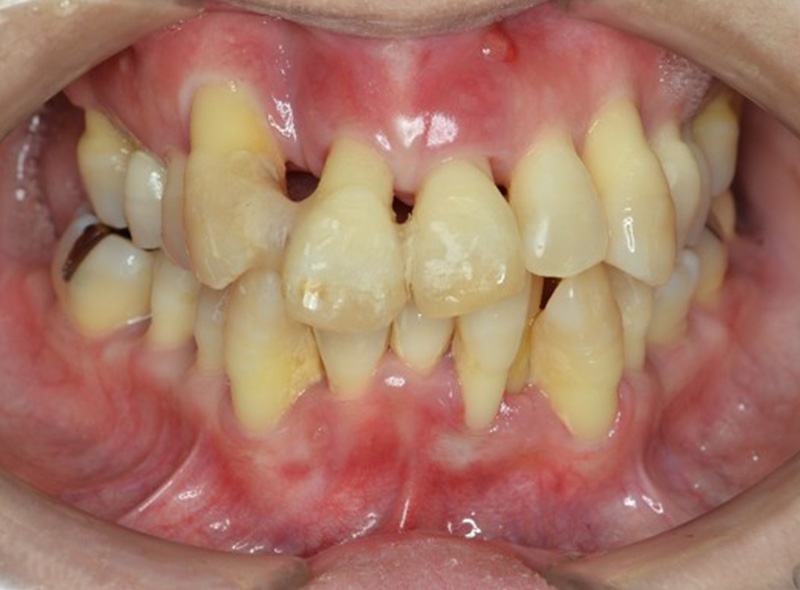

歯周再生療法 歯周矯正治療 ジルコニアセラミック治療

Before

After

| 主訴 | 歯がぐらぐらする。歯周病を治したい。 |

|---|---|

| 治療期間・回数 | 約2年・約15回 |

| 費用 | 2,300,000円 |

| デメリット・注意点 | 詰め物・被せ物の調整が難しく、割れた場合は再治療が必要。 |